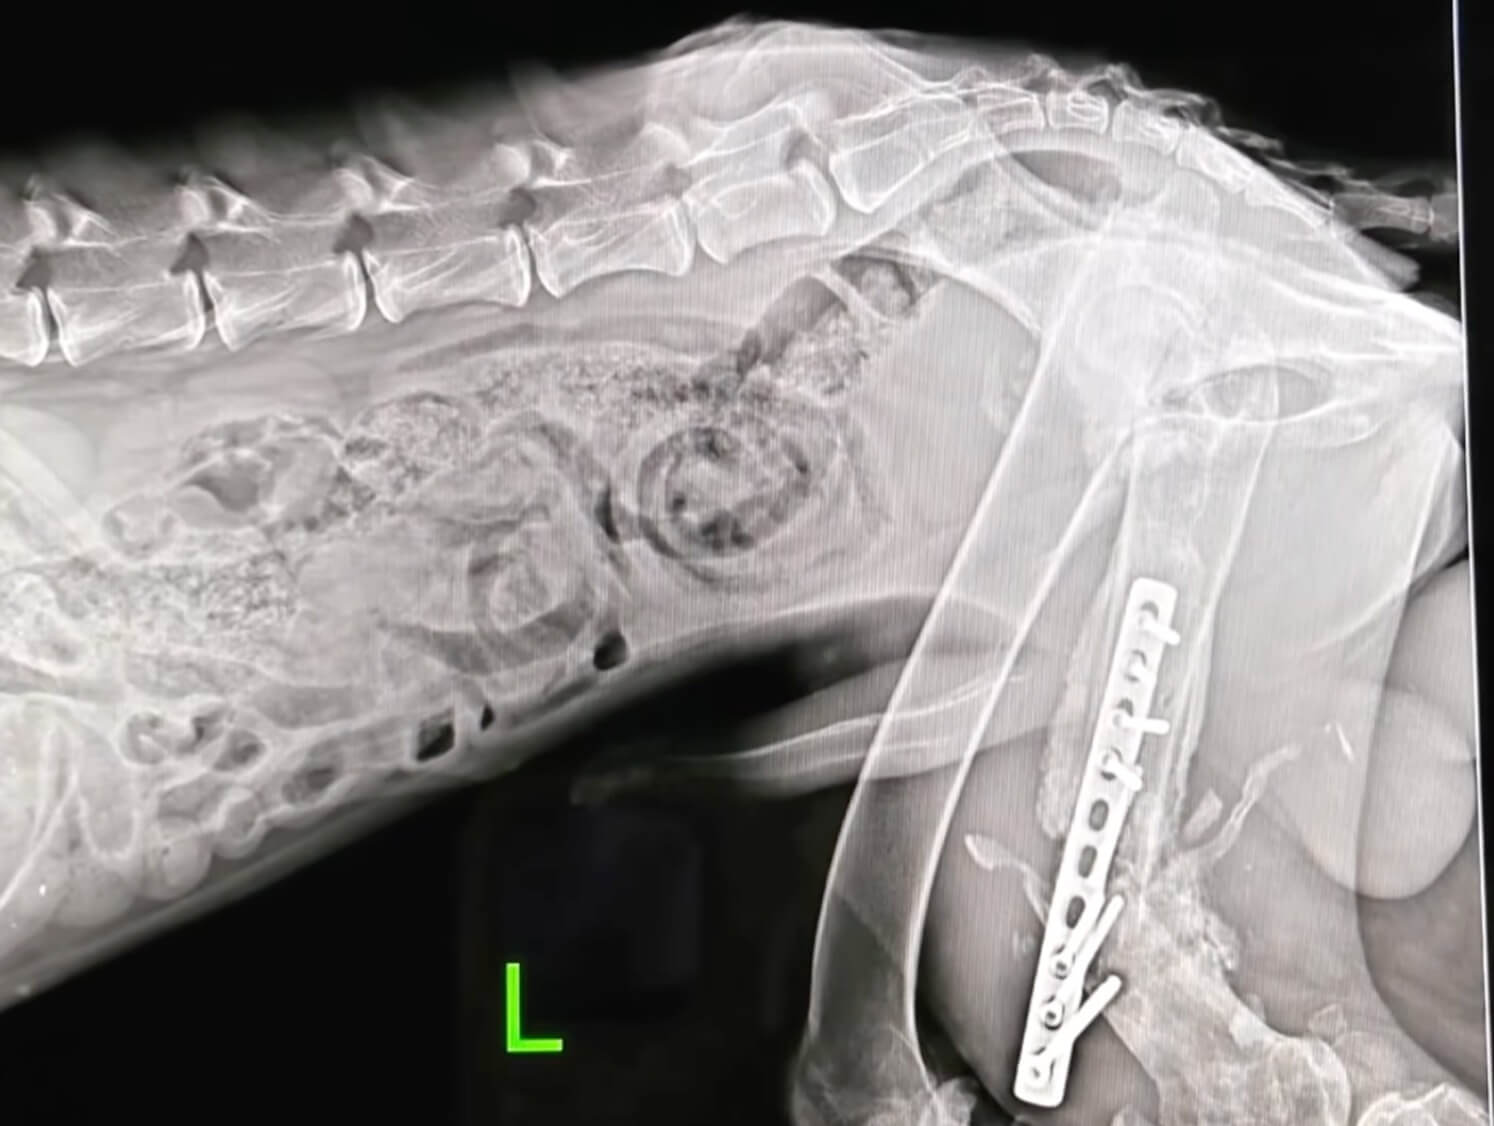

The Reality at the Clinic

At the veterinary hospital, the full picture came into focus.

His leg was fractured.

His muscles had weakened.

His body was struggling with nutritional imbalance, making recovery even harder.

Standing wasn’t just difficult.

It was impossible.

Just when things began to improve, another challenge came.

A complication meant he needed surgery again.

More waiting.